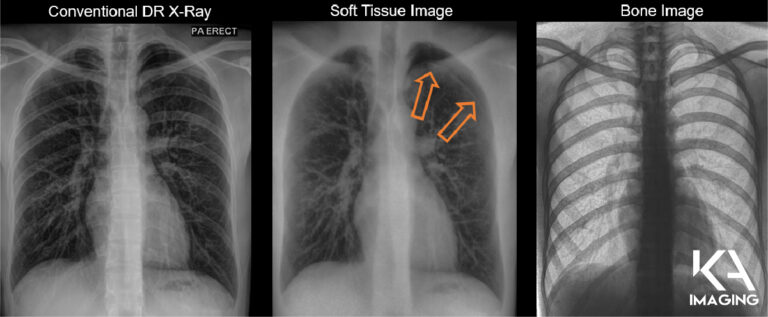

Karim S. Karim, CTO of KA Imaging: The biggest difference with dual energy is that you get better discrimination of soft tissue and bone. With the Reveal 35C technology we’re getting a regular X-ray, plus a soft tissue image and a bone image. The advantage of these spectral images, the soft tissue and the bone, is that you can visualize soft tissue without interference from the bone. You can visualize bone without interference from the soft tissue. For example: in the bone image you can see lines, tubes and calcified nodules beautifully; in the soft tissue image you can see pneumothorax and pneumonia quite nicely.

An X-ray image that improves the overall visualization will reduce the chance that small abnormalities would be missed, which means better outcomes for the patient and hospital. Also, spectral imaging lets you identify materials that regular X-ray imaging would not be able to. So for example, something that shows up in the bone image most likely is calcified like a calcified nodule, a calcified artery, a calcified vessel, and something that shows up in the soft tissue is soft tissue. In regular X-ray, you have to guess if a nodule is calcified or not. By material discrimination, you add an additional layer of analysis and data for the clinician, and it allows the clinician to make a better decision than they would if they were just looking at regular X-ray imaging, mobile or fixed.